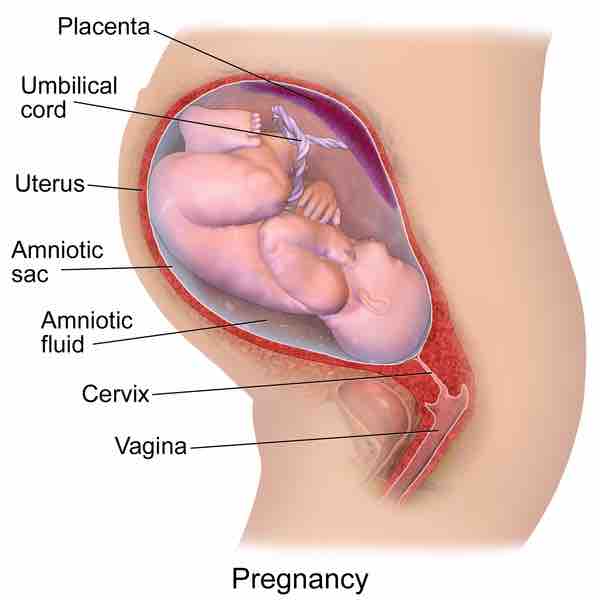

Pregnancy

Drawing of the lateral (side) view of a pregnant woman's abdomen revealing the developing fetus.